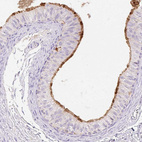

Immunohistochemistry analysis in human epididymis and pancreas tissues using HPA052921 antibody. Corresponding TMEM150C RNA-seq data are presented for the same tissues.